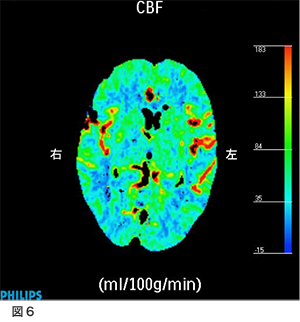

5.脳血流検査(CT perfusion)

手術で浅側頭動脈を中大脳動脈に吻合しました。本例では1本のみですが、症例により2本吻合する場合もあります。